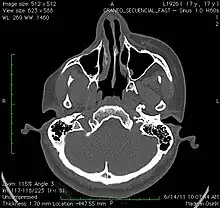

A 3D, soft tissue reconstruction of a CT scan of a 17-year-old girl with Parry Romberg syndrome.

CT scan3D bone reconstruction of a 17-year-old girl with Parry Romberg syndrome.